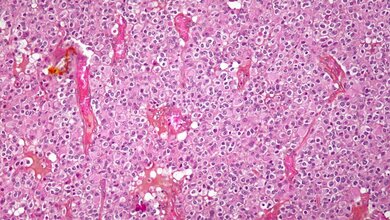

Dieselbe Forschergruppe veröffentlichte in Zusammenarbeit mit Prof. Martin Kocher vom INM-4 und der Kölner Universitätsklinik für Stereotaxie kürzlich eine weitere Arbeit. Die Hirnforscher zeigen im Fachjournal "NeuroImage: Clinical", dass sich eine Software darauf trainieren lässt, aufgrund von MRT- und FET PET-Bildern zwischen einer "Narbe" nach der Bestrahlung eines Hirntumors (Strahlennekrose) und einem erneuten Tumorwachstum zu unterscheiden. Auf konventionellem Weg mittels MRT ist diese Differenzierung kaum möglich. Sie ist aber wichtig, damit die Ärzte nicht Strahlennekrosen wie einen erneuten Tumor behandeln und damit den Patienten unnötig belasten.

Die entscheidenden Bildinformationen liefern wiederum die Texturmerkmale, die ein Arzt ohne Hilfe des Computers nicht erkennen kann. Die Jülicher Forscher fanden heraus: Die "Treffsicherheit" der künstlichen Intelligenz bei der Diagnostik verbessert sich auf über 90 Prozent, wenn sie mit MRT- und FET PET-Texturmerkmalen "gefüttert" wird. Muss sie mit den Texturmerkmalen von einer der beiden Tomografie-Methoden auskommen, liegt die diagnostische Genauigkeit immer noch bei rund 80 Prozent.